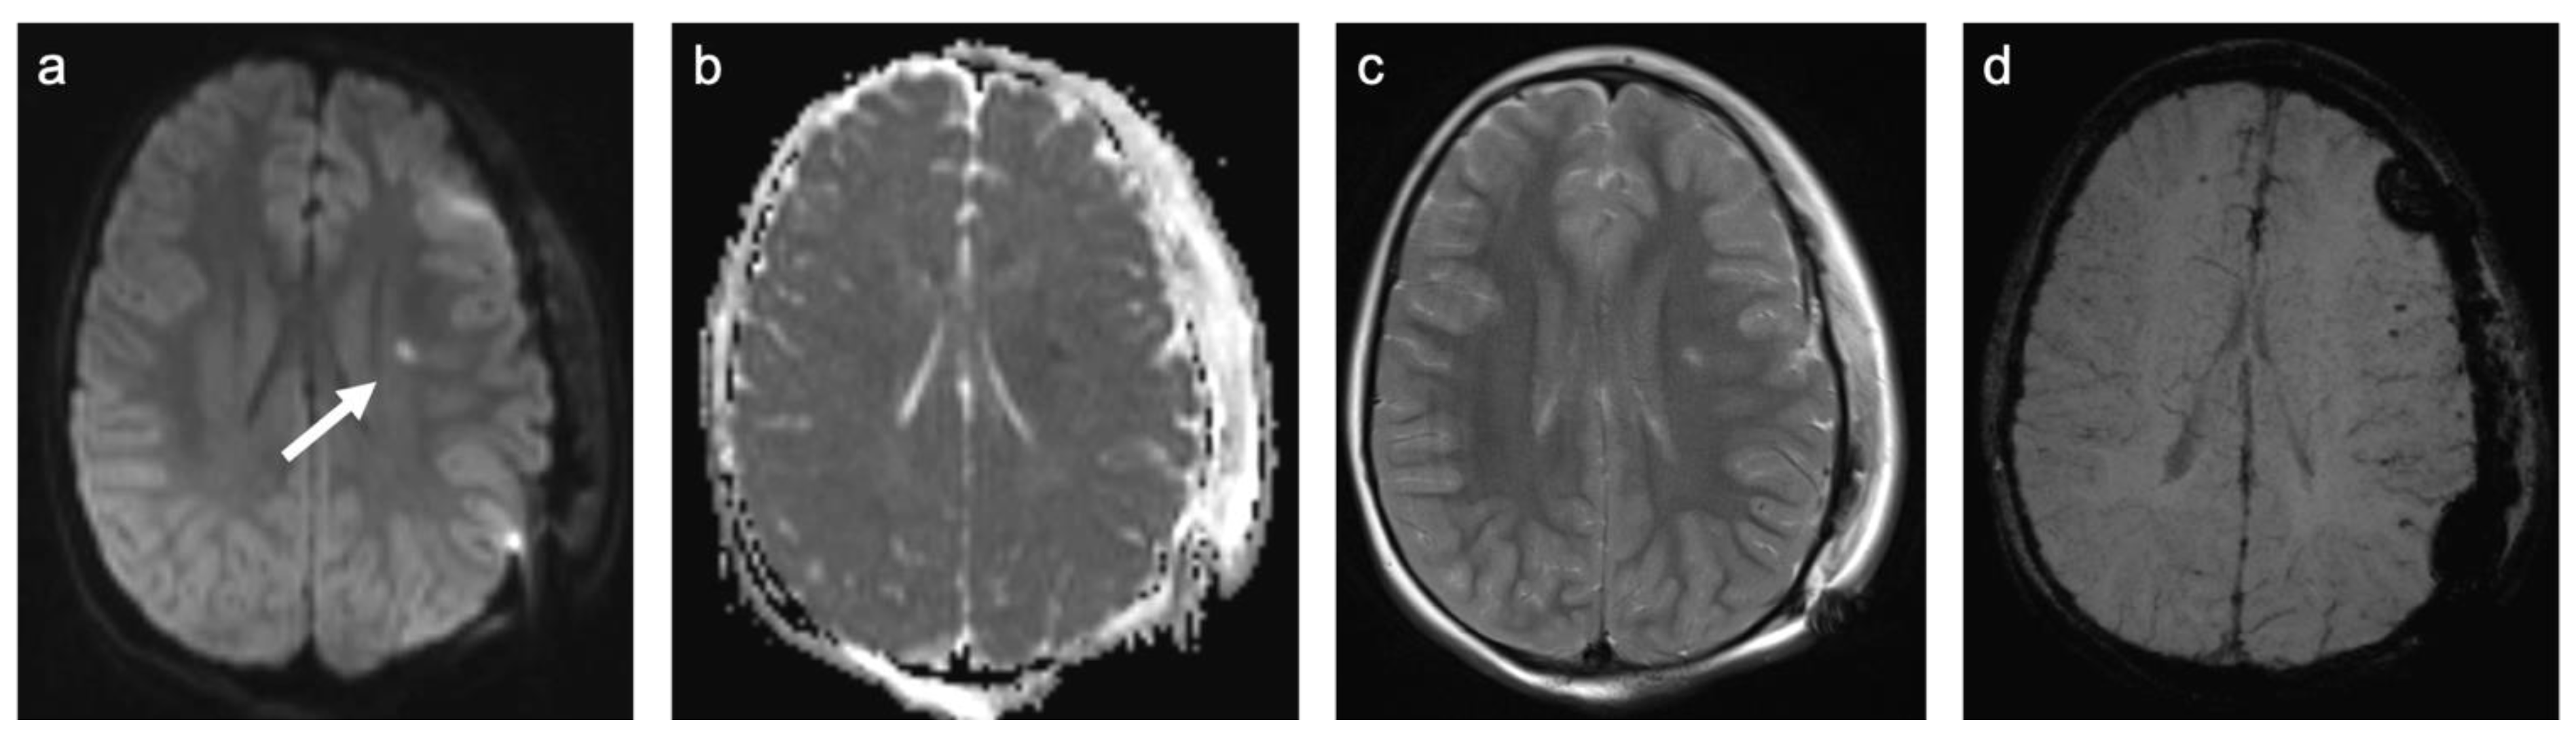

Group 2 consisted of 30 patients. Eight patients (27%) suffered from perinatal asphyxia; one of them was born preterm. Ten patients (33%) were diagnosed with periventricular leukomalacia (PVL); six of them were born preterm and two had co-occurring intraventricular hemorrhage (IVH). Ten patients (33%) showed signs of ischemic stroke. Eight of these strokes were of obscure or of unknown origin (cryptogenic). One was suspected to be cardio-embolic in a patient with a congenital heart disease with a ventricular septal defect in inherited Xq24 microdeletion syndrome and one as associated with sickle cell disease. The remaining two patients (7%) suffered from a cerebral venous sinus thrombosis with venous outflow obstruction leading to ischemia. A representative case is shown in Figure 4. In total, 60% of patients were female and the mean age was 7.8 years (min 3 days; max 18.4 years). A total of 57% of patients were examined with contrast-enhanced MRI and 12% of those examinations showed at least one enhancing lesion. WMSAs in this group of patients were localized supratentorial only. A total of 43% of patients had multifocal WMSAs.

Figure 4. Representative case “Non-genetic hypoxic and ischemic insults”: term-birth asphyxia. DWI/ADC (a,b), T2W (ce), FLAIR (f) sequences. Neonatal resuscitation after severe term-birth (40 weeks) asphyxia in a three-day-old girl. (ac). Treatment with therapeutic hypothermia. MRI shows predominantly white matter injury as one of the patterns identified in term-birth asphyxia [20]. The same girl examined again at the age of four years (df). MRI shows periventricular signal hyperintensities in T2W/FLAIR sequences.

Figure 5. Representative case “Traumatic white matter injuries”: diffuse axonal injury. DWI/ADC (a,b), T2W (c), and Susceptibility weighted imaging (SWI; (d)) sequences. Fourteen-year-old girl admitted after a traumatic car accident during which she was ejected from her seat. MRI shows a diffusion restricted, diffuse axonal injury lesion in the lobar white matter ((ac), white arrow). SWI demonstrates small regions of susceptibility artefacts at the grey–white matter junction corresponding to cerebral microbleeds (d). Additional findings are a subgaleal fluid collection (left side) following craniotomy for treatment of cranial impression fracture.